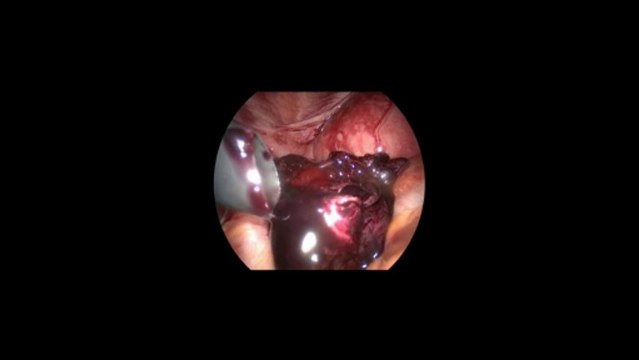

Salpingostomi yani tüpün çizilmesi yöntemiyle laparoskopik (kapalı ameliyat) dış (ektopik) gebelik ameliyatı

cemturan.com, Prof. Dr. Cem Turan: Salpingostomi yani tüpün çizilmesi yöntemiyle laparoskopik (kapalı ameliyat) dış (ektopik) gebelik ameliyatı videosu